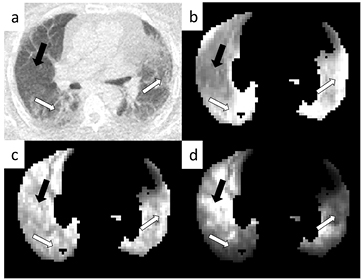

) for the NC, AFC and ABC cases for all six patients. It can be seen that in all patients the HD regions have a higher  than that of the LD region in the NC case (p = 0.01). After AFC, the regions become comparable with a p value of 0.35 and after ABC, the LD regions are significantly increased with respect to the HD regions (p = 0.01). Figure 2 is the SUV equivalent to figure 1 where it can be seen that the trend is similar to the

than that of the LD region in the NC case (p = 0.01). After AFC, the regions become comparable with a p value of 0.35 and after ABC, the LD regions are significantly increased with respect to the HD regions (p = 0.01). Figure 2 is the SUV equivalent to figure 1 where it can be seen that the trend is similar to the  case with the HD regions appearing significantly higher than the LD regions in the NC case (p = 0.0001), approximately equivalent after AFC (p = 0.092) and significantly lower in the ABC case (p = 0.0001).

case with the HD regions appearing significantly higher than the LD regions in the NC case (p = 0.0001), approximately equivalent after AFC (p = 0.092) and significantly lower in the ABC case (p = 0.0001).

Standard image High-resolution imageFigure 2. Bar graphs displaying the difference in SUV in fibrotic (light grey bars) and normal appearing regions (dark grey bars) determined from the mean of the HDMask and LDMask (with >5% fractional parenchyma volume threshold) over the final dynamic PET frame for all analysed patients. In the top chart, no corrections have been applied, the middle chart displays the values following AFC and the bottom chart is after ABC. Note that the SUV appears higher in fibrotic regions when compared to the normal appearing regions without corrections but lower after correction.

Standard image High-resolution imageFigure 3 displays an example parametric  image for each correction method. In the top left (a) the CT image can be seen displaying obvious regions of fibrosis (white arrows) and a region of normal appearing tissue (black arrow). In the top right (b) is the parametric image with no corrections displaying an apparent high influx rate in regions of fibrosis in comparison to those of normal appearance. In the bottom left (c) is the AFC image where the influx rate appears more uniform throughout the lung and after ABC (d) the regions of fibrosis appear to have a lower influx rate than those of normal appearance. Figure 4 displays the SUV results in the same layout as figure 3.

image for each correction method. In the top left (a) the CT image can be seen displaying obvious regions of fibrosis (white arrows) and a region of normal appearing tissue (black arrow). In the top right (b) is the parametric image with no corrections displaying an apparent high influx rate in regions of fibrosis in comparison to those of normal appearance. In the bottom left (c) is the AFC image where the influx rate appears more uniform throughout the lung and after ABC (d) the regions of fibrosis appear to have a lower influx rate than those of normal appearance. Figure 4 displays the SUV results in the same layout as figure 3.

Standard image High-resolution imageFigure 4. Example SUV images from a single patient. Image (a) is the CT as in figure 3(a). Image (b) is the uncorrected SUV image (grey scale 0–1.5 SUV), image (c) is the same image after AFC (grey scale 0–3.5 SUV) and image (d) after ABC (grey scale 0–12 SUV). All images are shown after whole lung masking with >5% fractional parenchyma volume thresholding.